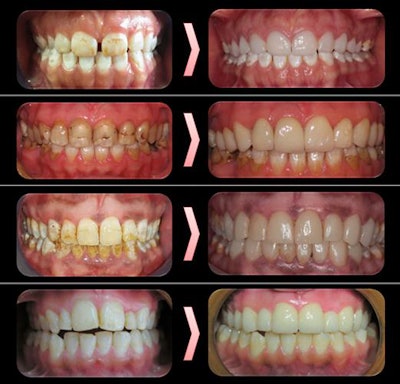

Before and after photos of patients at 10-year follow-up.The clinicians used disilicate reinforced glass-ceramic material to fabricate the veneers, then evaluated the restorations using U.S. Public Health Service criteria. Survival was defined as the time from cementation to failure of the veneer. Fracture of the ceramic and deterioration of adhesion were also considered veneer failure.

The estimated survival rate of the veneers in the study was 0.997 or greater for 10 years. Over the years, some teeth with veneers had fractures and secondary caries, the authors noted.